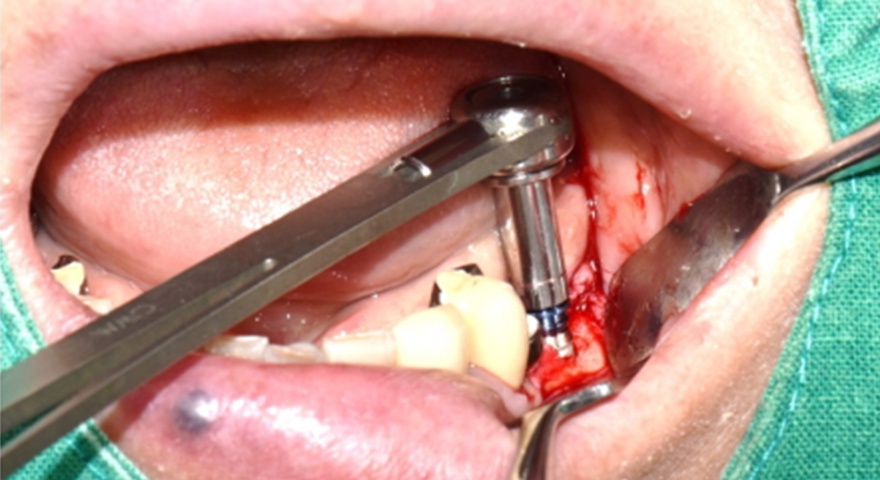

Після проведення стандартної імплантації в ділянках з оголеною різьбою було застосовано техніку DUK: на імплантат наносили спочатку пастоподібний матеріал, далі — гранули, після чого укладали мембрану та закривали клапті швами без натягу. Всі пацієнти отримували антибіотики (амоксицилін) та знеболення (ібупрофен), а через шість місяців — проходили контроль та біопсію ділянки.

Рис. 2. (A) Пацієнт із виявленою необмеженою (non-contained) втратою кісткової тканини та оголенням імплантату з букального боку на момент встановлення імплантату. (B) Нанесення основного шару пастоподібного кісткового матеріалу перед внесенням гранульованого кісткового трансплантата. (C) Укладання колагенової мембрани з покриттям зони трансплантації — від букального до піднебінного боку — та фіксували за допомогою внутрішніх періостальних швів. (D) Через шість місяців після аугментації — візуалізується регенерація кістки з букального боку в ділянці раніше оголеної різьби імплантату.